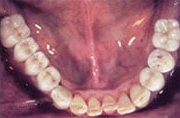

Unterkiefer mit Teilbezahnung

3 Implantate als Basis eingesetzt

Festsitzende Brücken und Kronen aufgesetzt